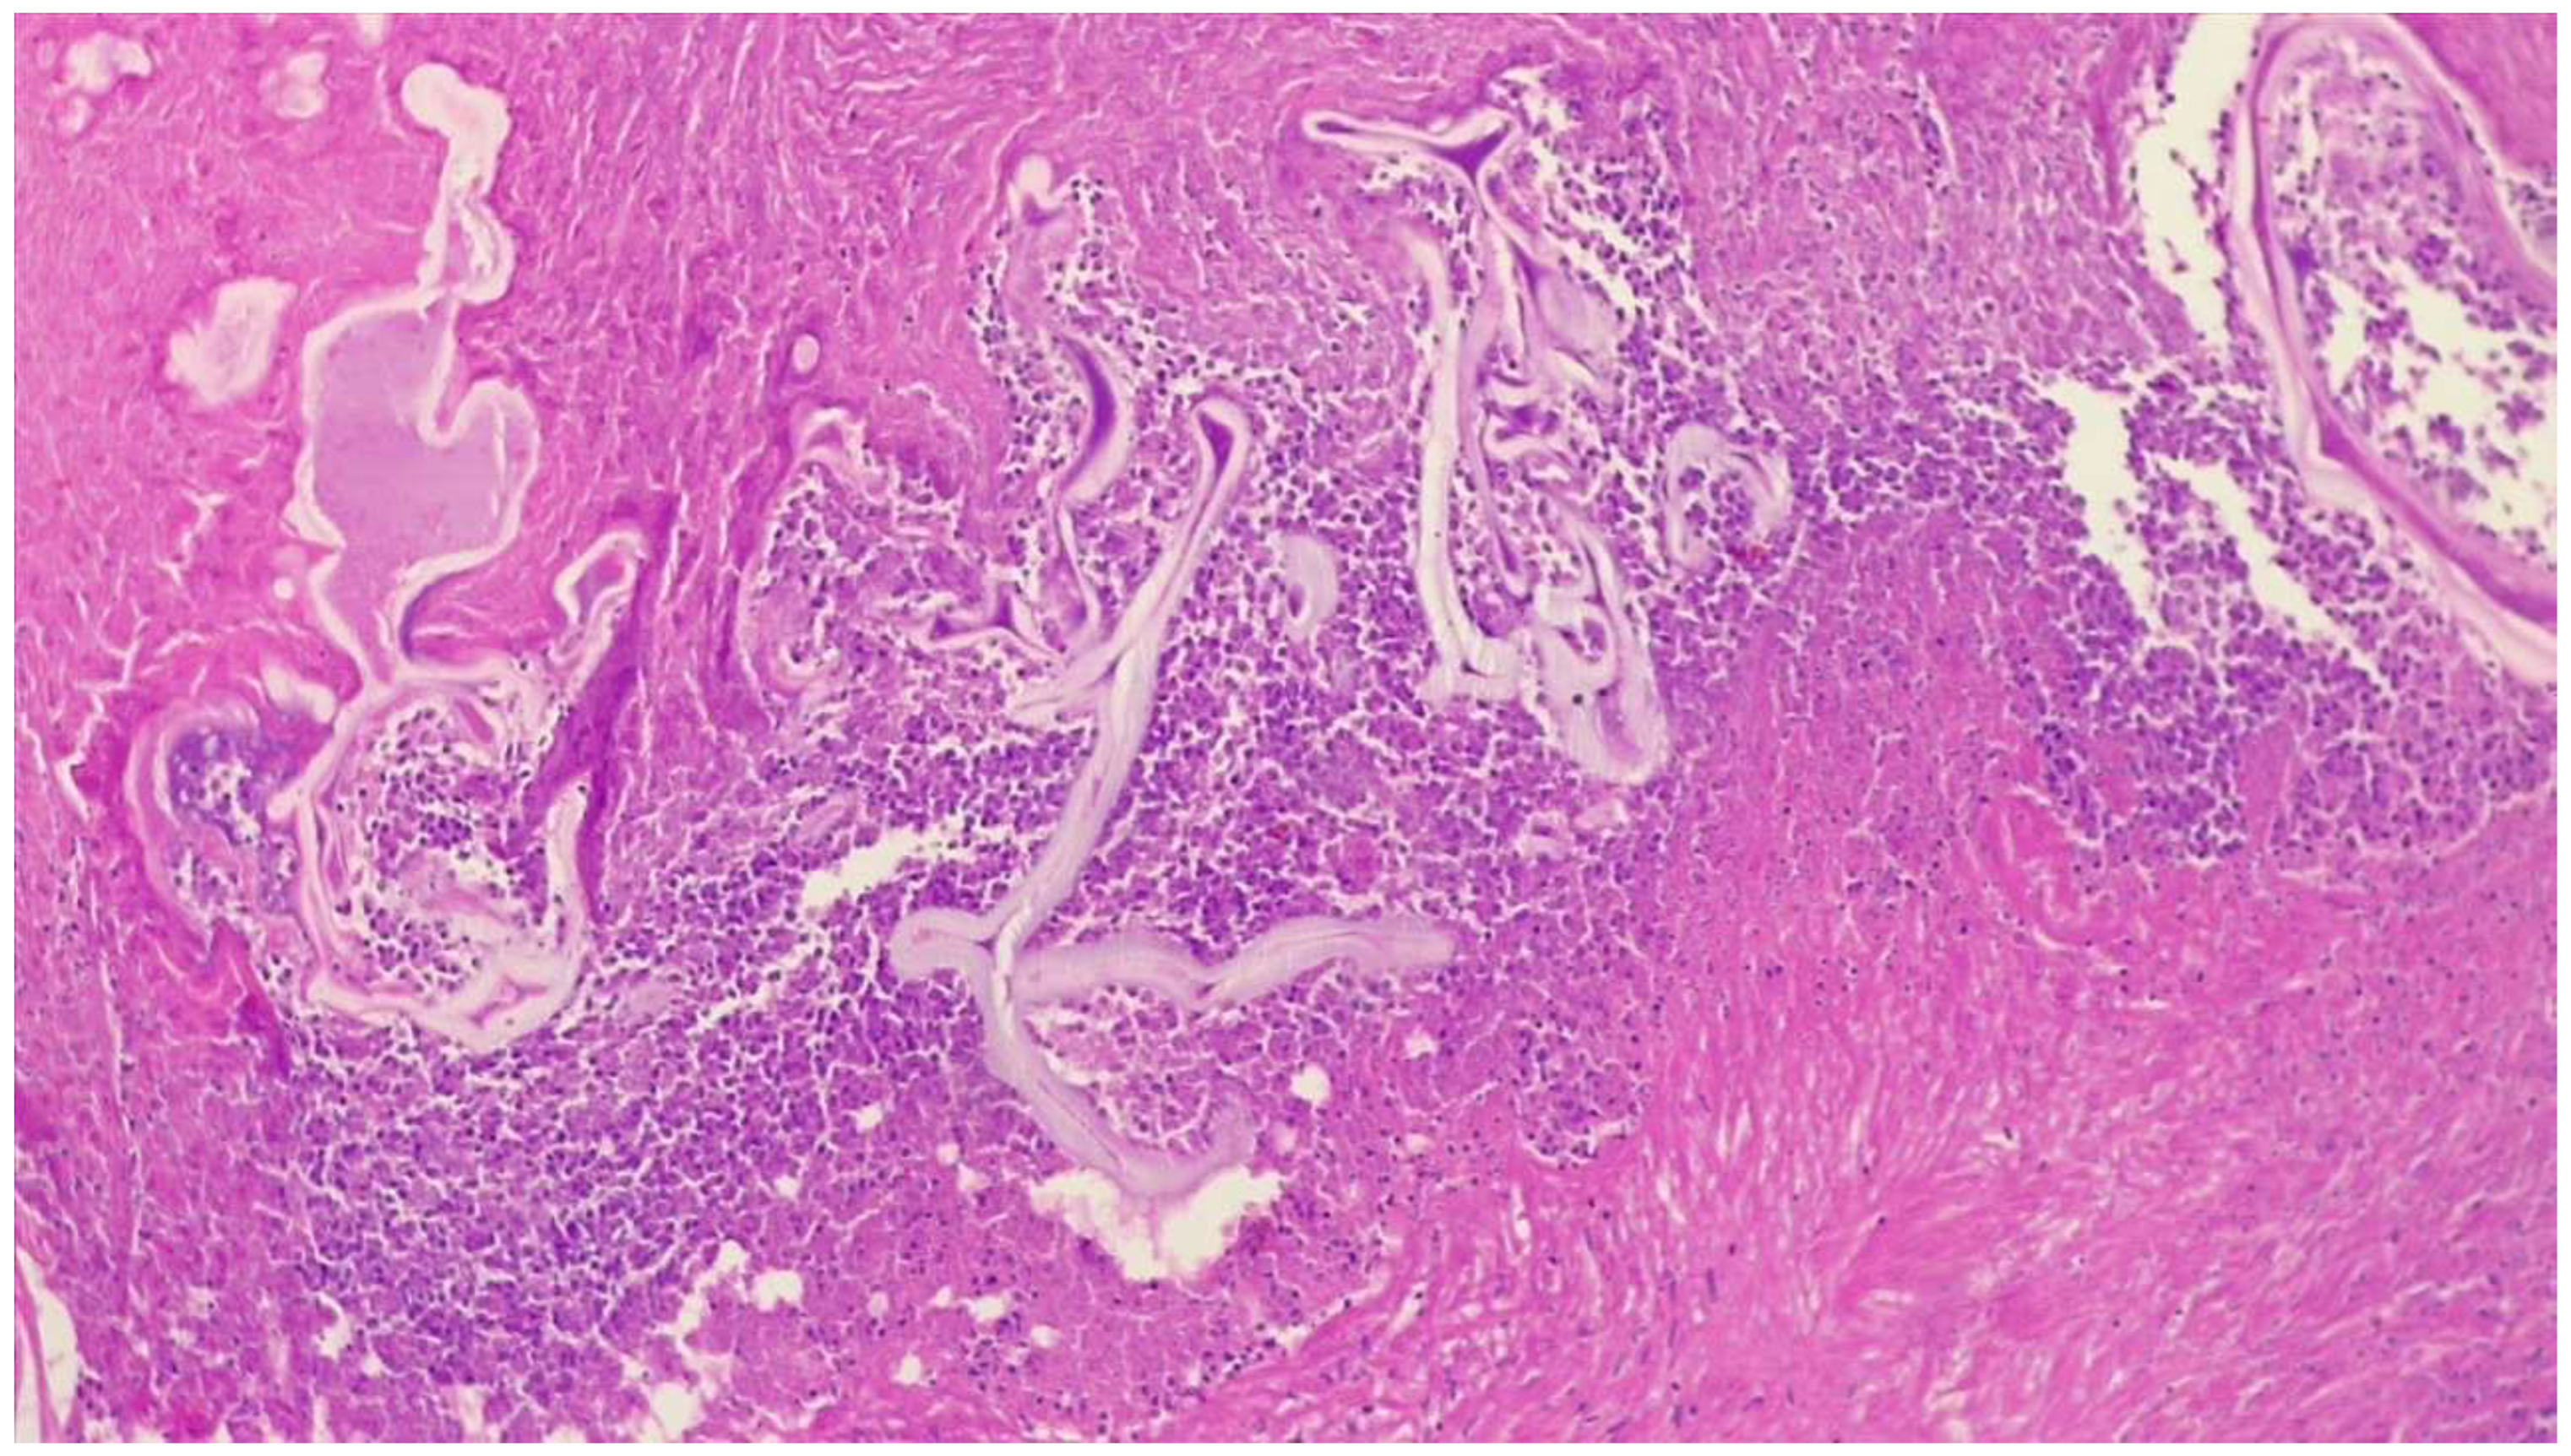

These were addressed synchronously with bilateral posterior thoracotomies in a prone position, using our experience in bilateral lung transplantation with this approach (left side: through the VII left intercostal space; right side: through the VI right intercostal space). Gentle manual palpation is necessary for localization. Wedge-type excisions were performed using standard automatic endostaplers of 45/60 mm length on clear macroscopic margins of minimum 1 cm interval (Figure 3). Histopathological confirmed extensive tissue necrosis and echinococcal structures (Figure 4). The parasite lesions may extend directly across the diaphragm and their rupture is a respiratory emergency.

Figure 4. Histopathological specimen of case 1. Multiple cystic cuticular structures surrounded by abundant necrotic tissue and inflammatory reaction. Other areas showed in addition granulation tissue and fibrosis (H&E staining, 100×).